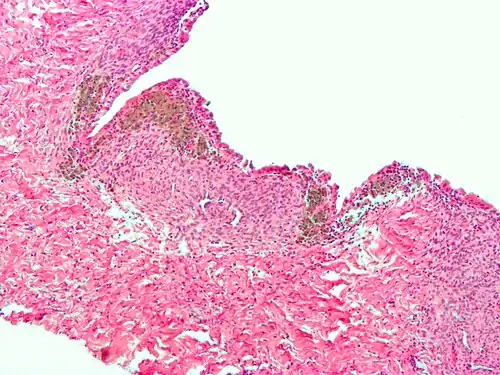

For a histopathological diagnosis, at least two of the following three criteria should be present:[121]

- Endometrial type stroma

- Endometrial epithelium with glands

- Evidence of chronic hemorrhage, mainly hemosiderin deposits

Immunohistochemistry is useful in diagnosing endometriosis as stromal cells have a peculiar surface antigen, CD10, thus allowing the pathologist go straight to a staining area and confirm the presence of stromal cells and sometimes glandular tissue is identified that was missed on routine H&E staining.[122]

Micrograph of the wall of an endometrioma. All features of endometriosis are present (endometrial glands, endometrial stroma and hemosiderin-laden macrophages).